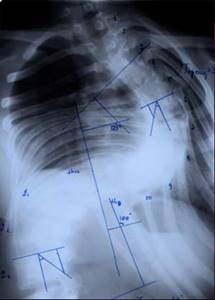

| Больная Л-ч, 12 лет сколиоз IV степени |

Результат оперативного лечения |